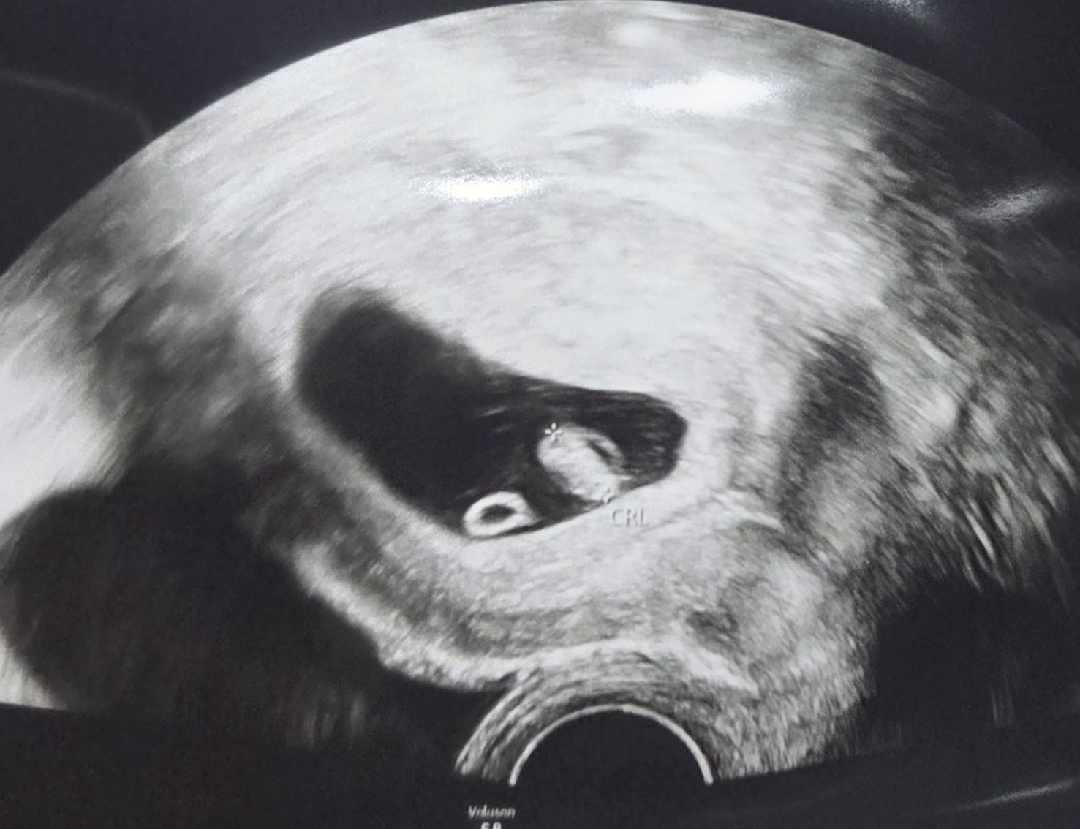

예정일 4월 14일에서 4월 12일로 당겨졌어요! 고리모양의 난황이 아기 밥상처럼 있어서 너무 귀엽네여 ㅎㅎ

ㅎㅎ난황이 밥상처럼 너무 귀엽네요